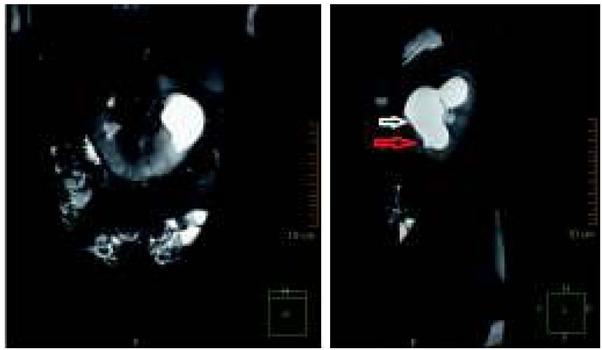

Ryc. 2

Ryc. 3